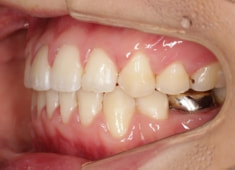

治療開始時

治療中